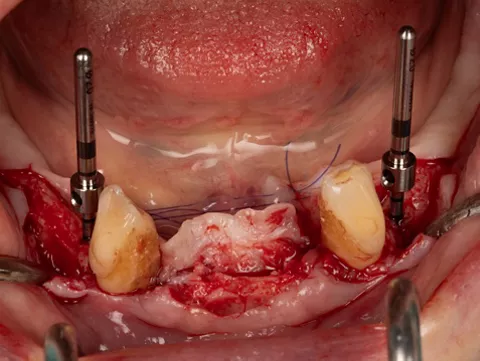

3c. Two mini-implants with a diameter of 2.6 mm and a length of 12 mm were placed in positions 32 and 42, first manually and then using a contra-angle. The insertion torque recorded at the end of the procedure was 21 N.cm in 32 and 17 N.cm in 42. The implants were positioned 0.5 mm subcrestal, i.e. with slight burial of the smooth neck.

3c

3d

3d. Two mini-implants with a diameter of 2.6 mm and a length of 12 mm were placed in positions 34 and 44 using the same protocol as for the previous mini-implants. The torque obtained was 27 Ncm in 34 and 37 Ncm in 44.